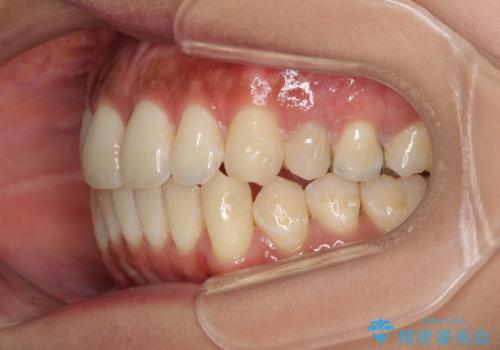

八重歯の再矯正 インビザラインでストレスなく矯正治療

- 学生の頃に矯正治療を行ったものの、保定を怠けてしまったことによる後戻りを気にして来院された患者様です。

根管治療が必要な歯があったため、矯正治療前に根管治療を行い、その後はインビザラインにより矯正治療を行うこととしました。

下顎の八重歯が上顎歯列に収まる過程で咬みにくさがありましたが、最終的には、咬み合わせも安定し、きれいに歯列を整えることができました。